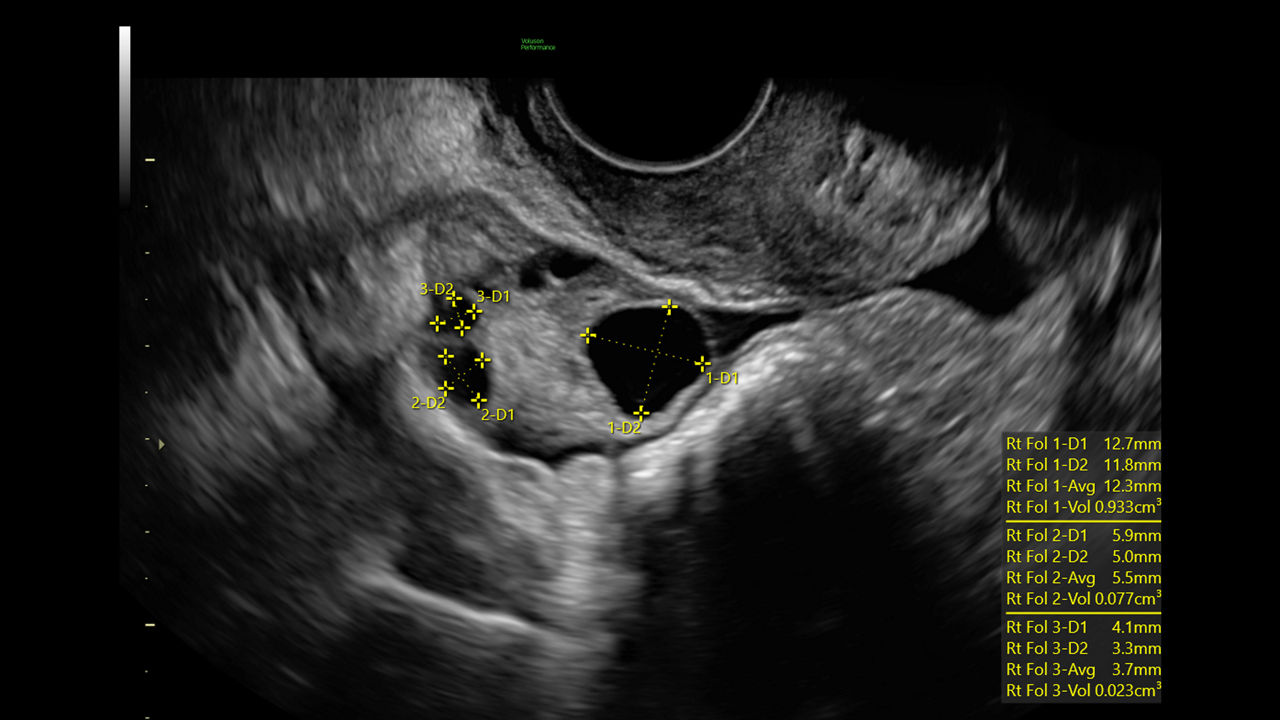

At a glance

Enhance your workday with leading AI-based technology and progressive tools that simplify and speed up exams. Automate manual tasks and calculations to save time, increase consistency, and improve accuracy.

Segment fibroids with 88% accuracy using Fibroid Mapping